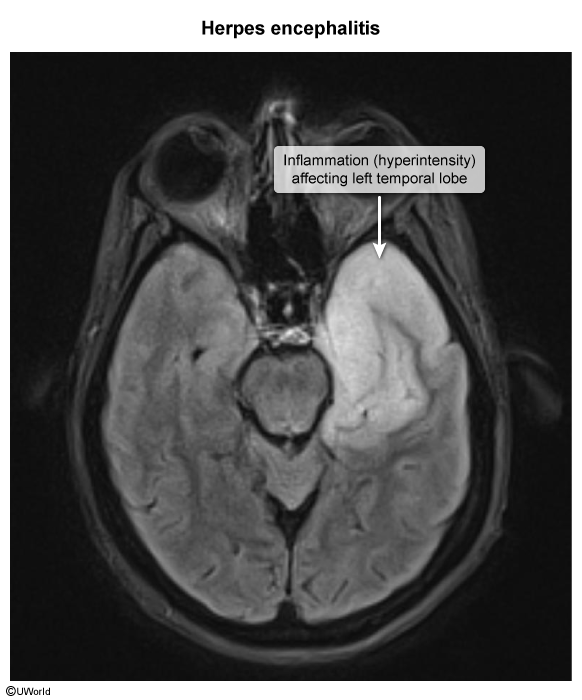

- MRI head

- Characteristic features include signs of unilateral or bilateral temporal lobe edema and/or hemorrhage.

- T2/FLAIR sequence: hyperintense temporal lobe lesions and signal abnormalities